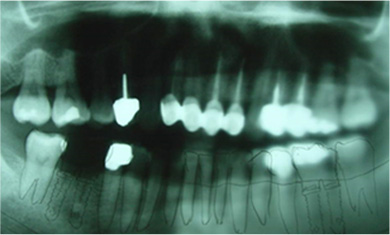

咬合崩塌 / 上牙下墜 / 下牙上長 / 前牙飆出 / 傾倒 / 蛀牙 / 牙周病缺牙未重建 - 臨床實例

上面的牙往下墜,下面的牙往上長,前面的牙往外飆 – 咬合崩塌牙周病,蛀牙;這些現象必然發生,時間越久,問題越大,而且除非藉由矯正及其他牙科治療,無法修正。